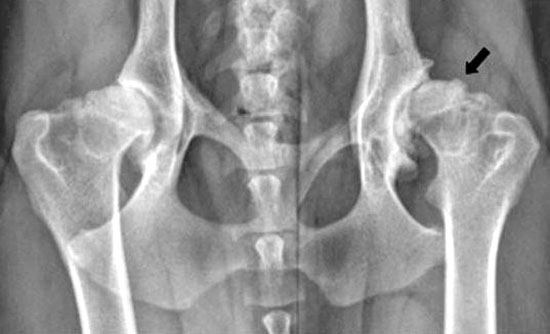

La

radiografia (raggi X) di un cane adulto e maturo con patologia

articolare degenerativa secondaria a displasia dell'anca cronica. La

testa del femore (freccia) e dell'acetabolo sono gravemente artritici,

come dimostra la testa appiattita del femore, del collo del femore

addensato, numerosi osteofiti, e poco profondo, acetabolo sclerotico.